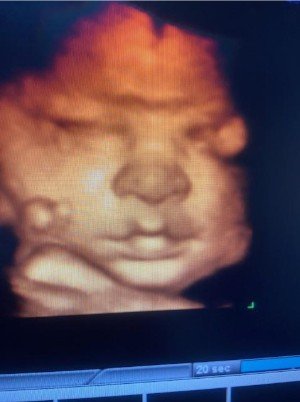

La atención incluye ecografías periódicas con tecnología 4D, ofreciendo imágenes y vídeo para que los futuros padres puedan ver la evolución del bebé con la máxima calidad. Estas exploraciones permiten valorar con detalle su crecimiento, posición y bienestar general.

Cara a las 23 semanas

Cara